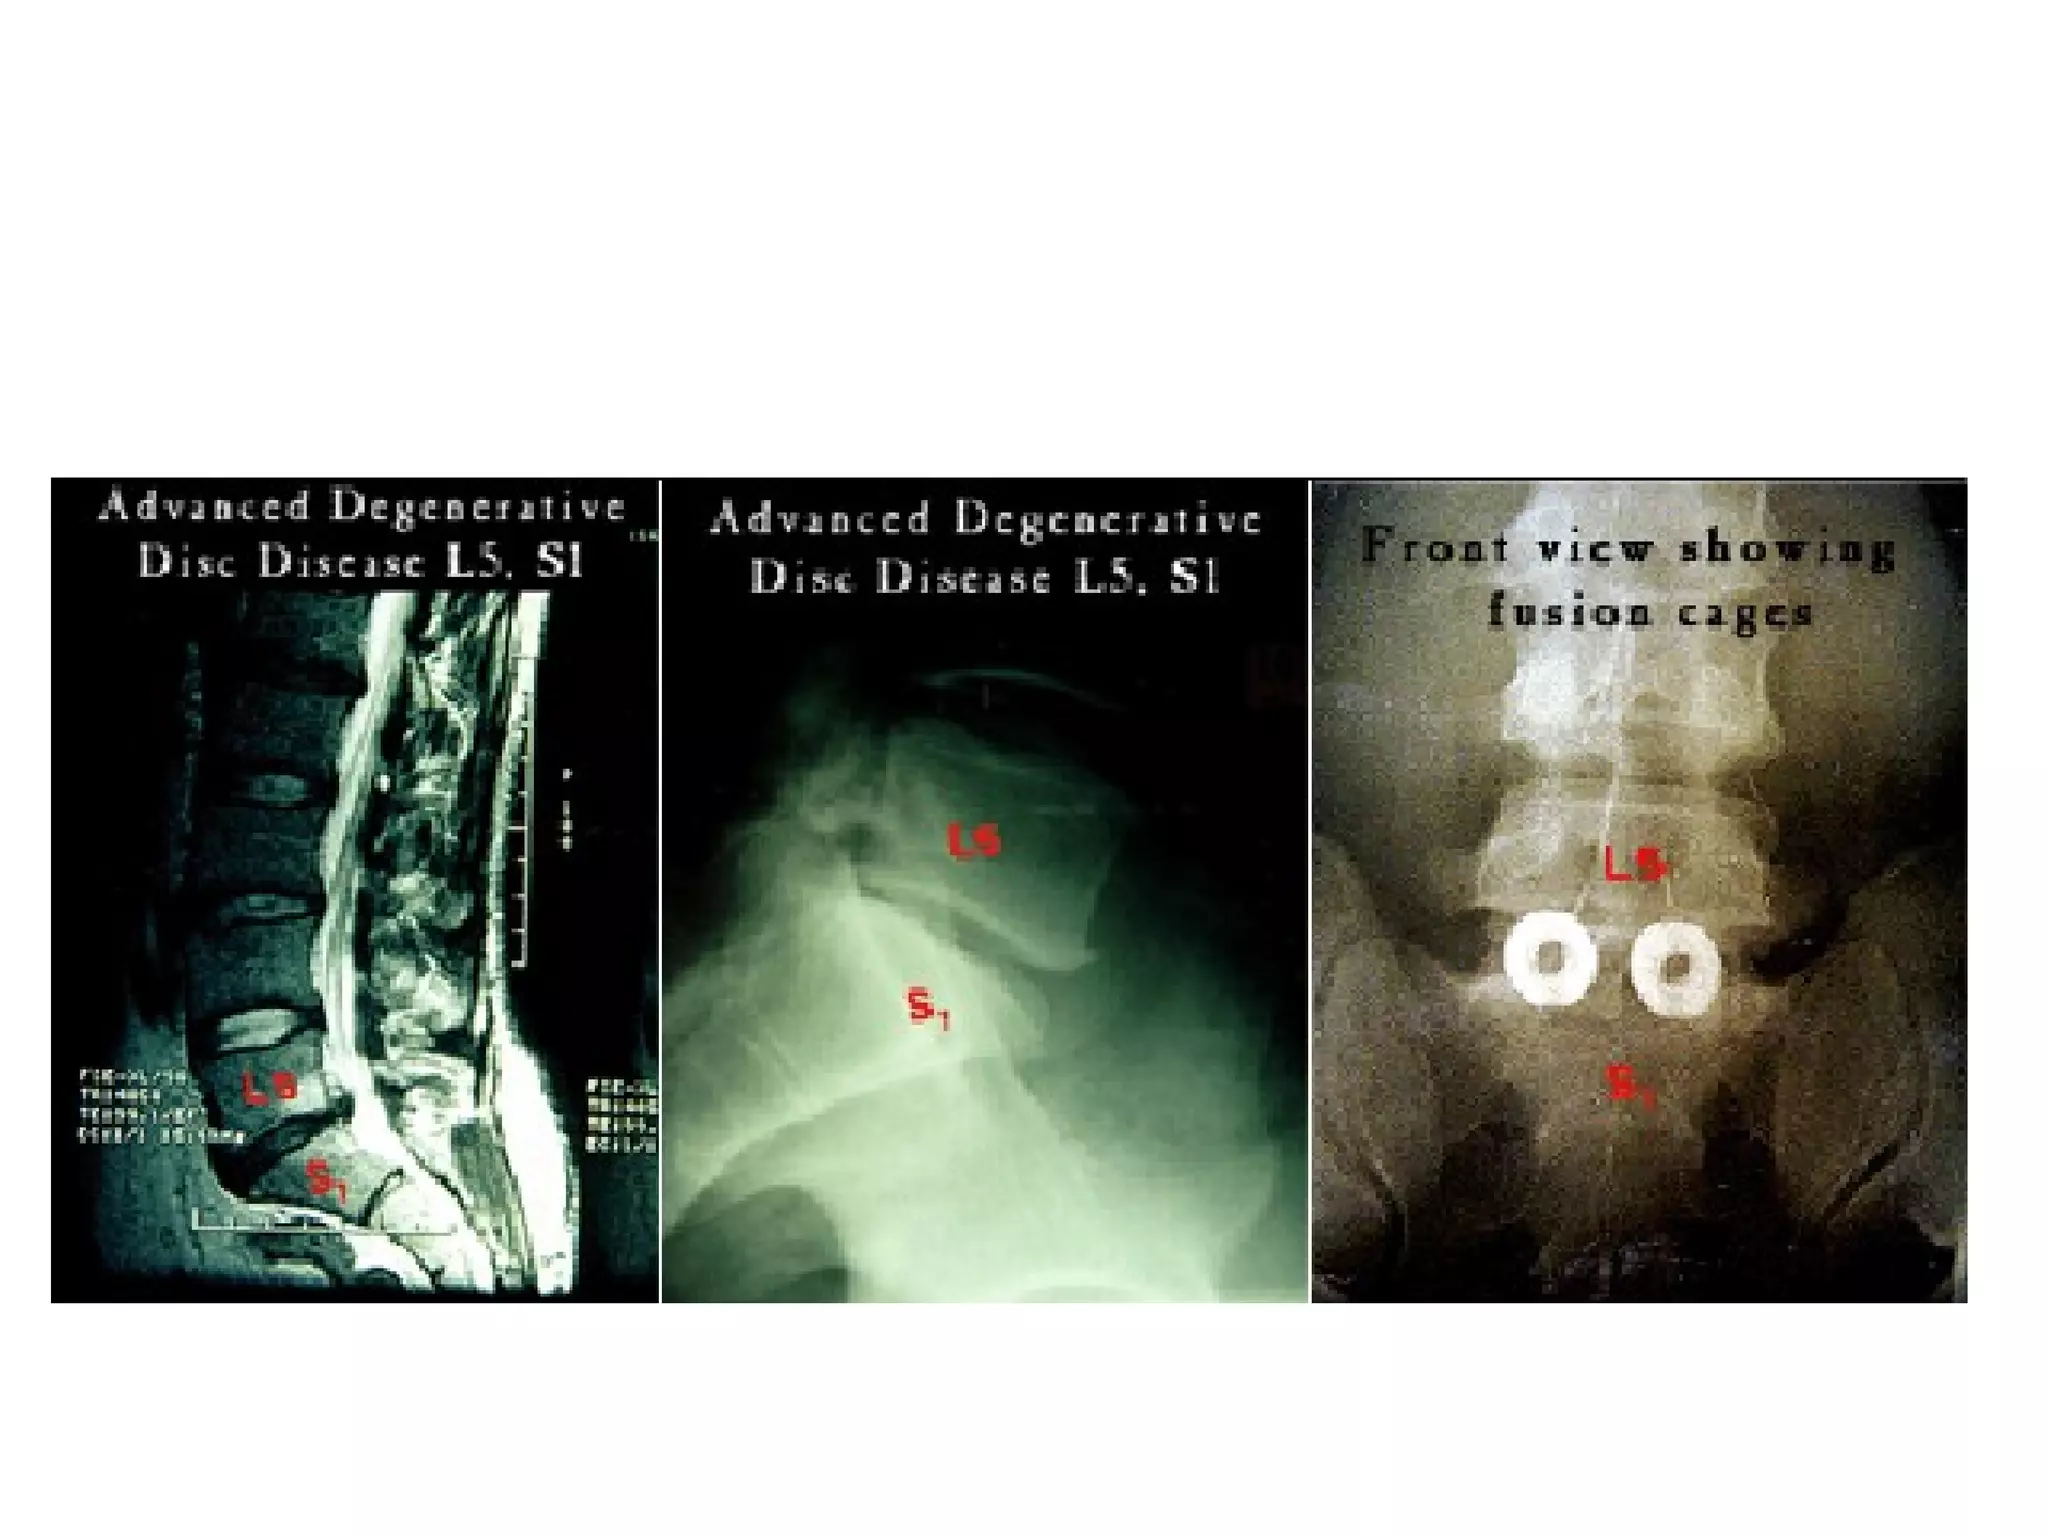

• Patients treated with anterior lumbar interbody fusion for

LBP, with type 1 Modic changes had much better

outcomes than those with isolated DDD and those with

type 2 changes, in whom the results were generally poor

• Fusion accelerates the course of type 1 Modic changes

probably by correcting the mechanical instability and that

these changes appear to be a good indicator of

satisfactory surgical outcome after arthrodesis